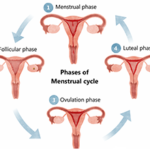

Causes Of Irregular Periods – Doctors Tips to Patients?

Author: Dr. Sharvari Mundhe MBBS, MS,DNB, FRM,DRMConsultant: Gynaecologist & Fertility Specialist at Motherhood Hospital Sarjapur, Bangalore Menstrual cycles are a natural and integral part of a woman’s reproductive health. However, many women experience irregular periods at some point in their lives. Irregular menstrual cycles, characterized by cycle length, duration, and flow variations, can be disruptive […]

Ovulation Symptoms: 10 Signs of Ovulation for Pregnancy

Author: Dr. Madhushree Vijayakumar MBBS, MRCOG, FRCOG, DGOConsultant: Obstetrician and Gynecology at Motherhood Hospital Hebbal, Bangalore What is Ovulation? A developed egg is released from one of the ovaries at the crucial stage of ovulation, which is part of the female menstrual cycle. The ovulation cycle’s core function is controlled by a complicated interaction of […]

How Does an Ovulation Calculator Work?

Author: Dr Ekawali Gupta MBBS, MS Degree in OBG from IGMC (Shimla) Consultant: Obstetrician and Gynecology at Motherhood Hospital Mohali An ovulation calculator can estimate when ovulation is most likely to occur based on the normal length of a woman’s menstrual cycle. Here’s a lowdown of how ovulation calculator works: 1. The day before a […]

Benefits of Using an Ovulation Calculator

Author: Dr. Madhuri Vidyashankar. P MBBS, MGO, FGO, DGOConsultant: Obstetrician and Gynecology at Motherhood Hospital Indiranagar, Bangalore Using an ovulation calculator can offer several benefits, particularly for women who are trying to conceive. Here are some of the key advantages: Predicting Fertility Window: The ability to pinpoint the most fertile days of a woman’s menstrual […]

When & How to Use Ovulation Calculator & Calendar

Author: Dr. Sharvari Mundhe MBBS, MS,DNB, FRM,DRMConsultant: Obstetrician and Gynecology at Motherhood Hospital Sarjapur Bangalore Ovulation calculator, also known as an ovulation day calculator or ovulation date calculator, is a tool specifically designed to predict the ovulation period based on the length of your menstrual/period cycle. Due to its ability to pinpoint the days of […]